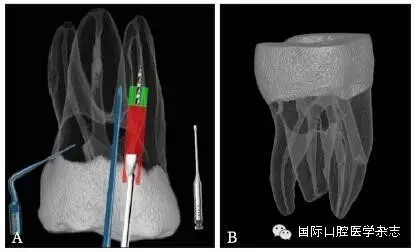

為了盡可能地減少牙本質(zhì)的損失量,應(yīng)當(dāng)根據(jù)分離器械的斷端直徑選擇合適尺寸的超聲工作尖或者環(huán)鉆,然后根據(jù)計(jì)算公式:D≥D1+D2(×2)計(jì)算選擇合適型號(hào)的GG鉆,創(chuàng)造相應(yīng)大小的平臺(tái),為后續(xù)分離器械的取出建立直線通路。其中,D為GG鉆的理論最小直徑,D1為分離器械的末端直徑,D2為超聲工作尖的直徑或環(huán)鉆壁的厚度。當(dāng)超聲工作尖僅在分離器械一側(cè)運(yùn)動(dòng),則公式中D2不需要(×2)(圖6)。具體要點(diǎn)詳見4.1。

A:D1為分離器械的末端直徑,D2為超聲工作尖的直徑或環(huán)鉆壁的厚度;B:當(dāng)超聲工作尖僅在分離器械一側(cè)運(yùn)動(dòng),則公式中D2不需要(×2)。

圖 6 GG鉆理論最小直徑的計(jì)算